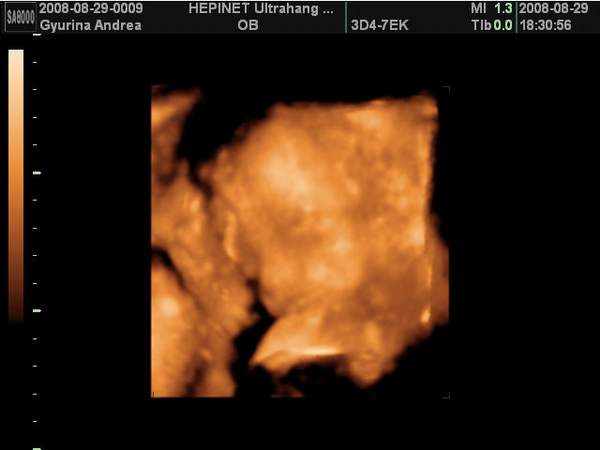

Én pénteken voltam 4D UH-on és végre megláttam a picurkám pofiját, ami szakasztott olyam, mint a nagyfiamé volt pinduri korában. Hát igen, van egy "nagy" fiam és lesz egy "kis"fiam is. Egyáltalán nem bánom, hogy fiú lett, majd a harmadik tuti lány lesz... :D

Dobok róla néhány képet, ha nem baj.

Kép Térd szaglászás...

Kép Nagyon töri valamin a buksiját...

Kép